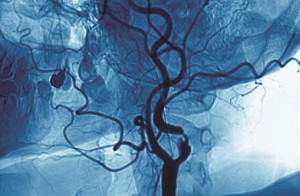

A heart attack occurs when one of the coronary arteries becomes blocked. Because of the blockage, the heart muscle can’t get its vital blood supply and will begin to die because it is not getting enough oxygen, if left untreated. The person will probably be conscious – you should call 999 and keep them calm.

Heart attacks are divided into STEMI and nSTEMI, according to how they show up on the ECG. STEMI occurs when there is a total blockage in a coronary artery that sends blood to the heart muscle. NSTEMI, which is more common, is a partial blockage of one or more arteries. Both result in serious damage to the heart muscle, and any heart attack is an emergency, though nSTEMI has a worse long-term prognosis.